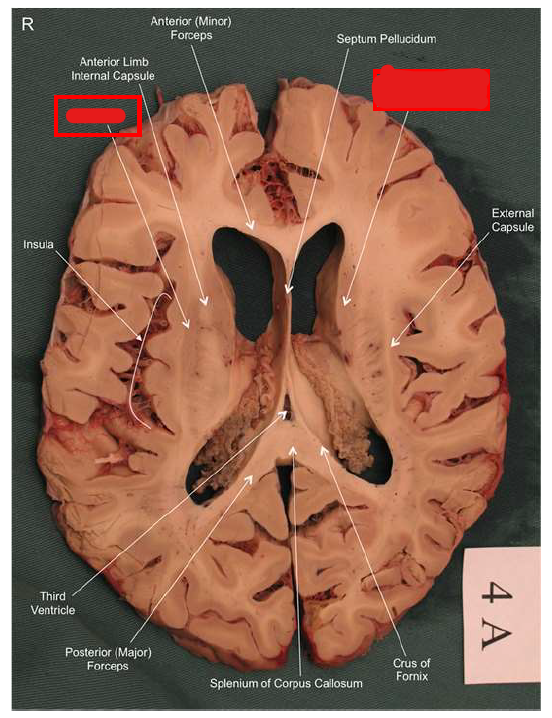

What structure is the major input to the basal ganglia?

striatum